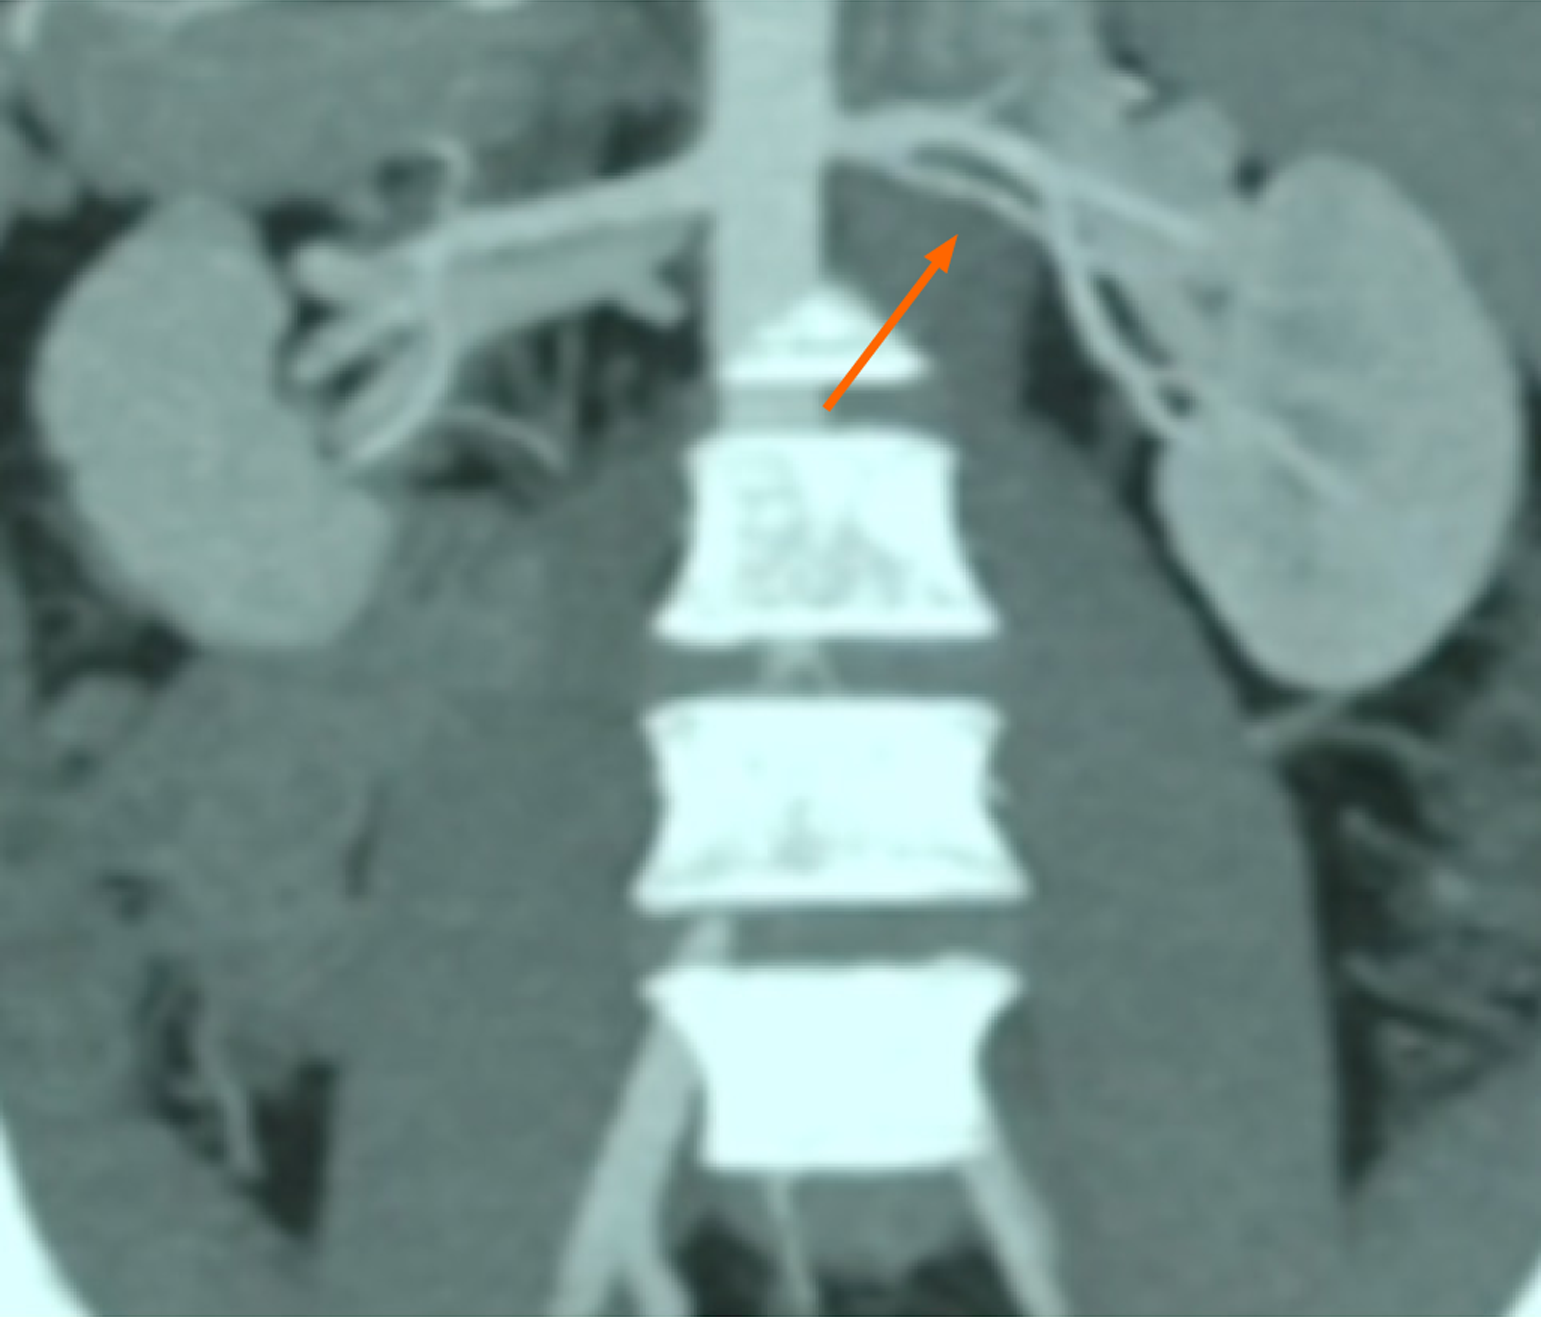

Preoperative abdominal computed tomography (CT) angiography confirmed suitable iliac vessel anatomy in the recipient for transplantation. However, the donor kidney demonstrated a short right renal artery (Figure 1).

A standard hard-assisted laparoscopic living donor nephrectomy was performed to retrieve the left kidney. Preoperative CT imaging revealed that the donor kidney had a renal artery with an early bifurcation (Figure 1). During the procedure, an endovascular stapler was applied distal to the bifurcation, resulting in a reduction of the arterial length by approximately 10-15 mm (Figure 2).